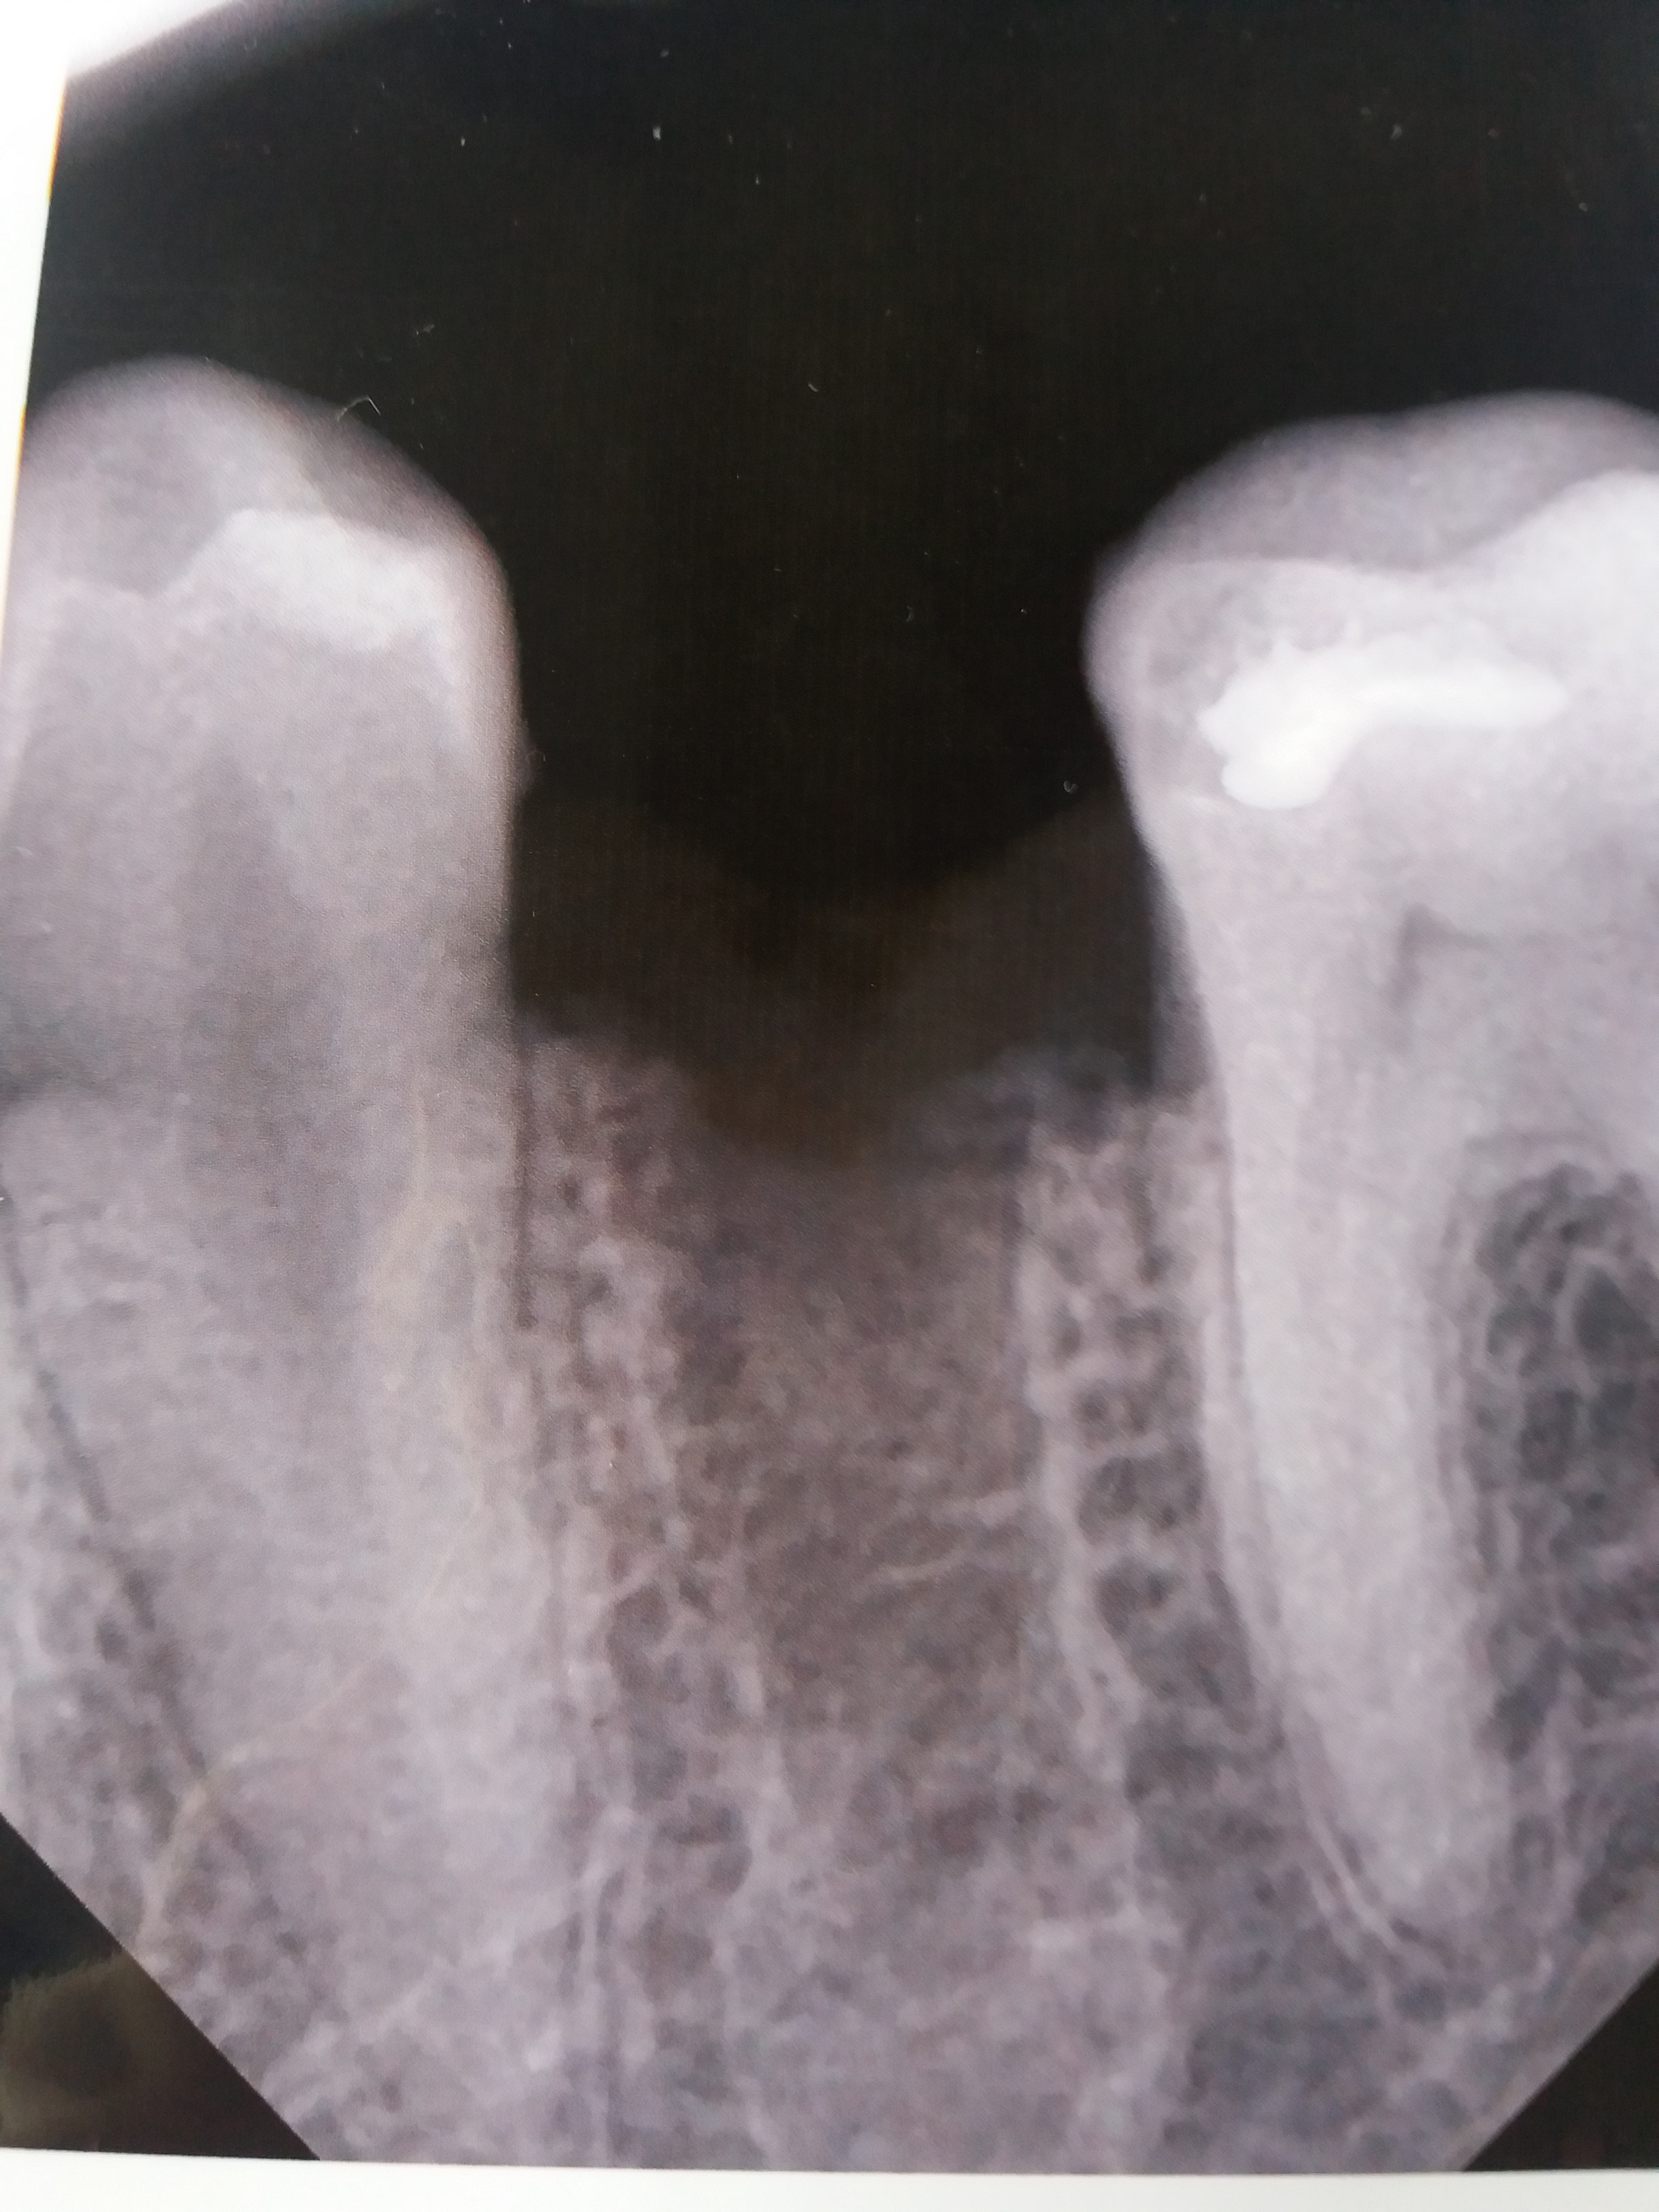

Киста зуба

удалили зуб с кистой, но похоже что она осталась на месте, возможно ли это? врач говорит что киста должна выйти вместе с зубом